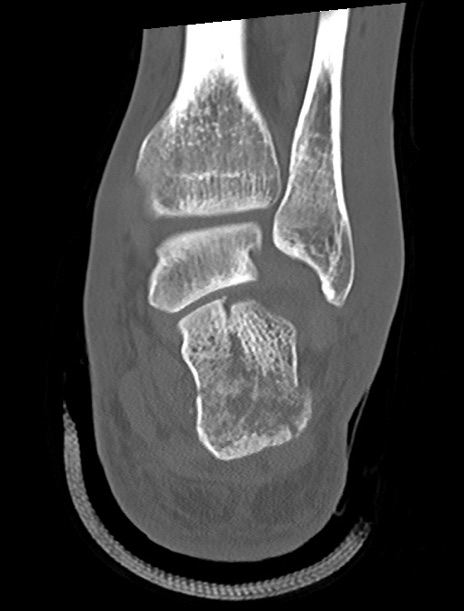

左足関節CT

矢状断像